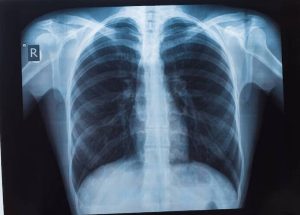

รศ.นพ.ศิระ เลาหทัย ศัลยแพทย์ทรวงอกจากศูนย์ผ่าตัดส่องกล้อง โรงพยาบาลวชิรพยาบาล กล่าวว่า มีคำถามยอดฮิตที่ว่า “เจอจุดที่ปอด (lung nodule) มีโอกาสเป็นมะเร็งกี่เปอร์เซ็นต์?” นั้นหลายครั้งที่เราไปตรวจสุขภาพแล้วพบเจอฝ้าขาว เมื่ออ่านผลรังสีวินิจฉัยพบเจอความผิดปกติในฟิล์มเอกซเรย์ปอด ทั้ง ๆ ที่เรายังไม่มีอาการผิดปกติใด ๆ เลย

สิ่งที่สำคัญที่สุด ก็คืออย่าเพิ่งตกใจเราต้องหาสาเหตุของจุดที่เกิดขึ้นมีจริงหรือไม่ โดยวิธีการที่หาสาเหตุที่ดีที่สุดคือการทำเอกซเรย์คอมพิวเตอร์(CT scan) แต่ไม่ควรที่จะทำเอกซเรย์ซ้ำ เพราะไม่เกิดประโยชน์ เนื่องจากการทำฟิล์มเปรียบเสมือนการถ่ายภาพ 2 มิติ เห็นแค่ด้านหน้า-หลัง ส่งผลทำให้เกิดผลภาพลวงได้บ่อย เปรียบเทียบกับการทำเอกซเรย์คอมพิวเตอร์เห็นรายละเอียด เป็นลักษณะของก้อนเนื้อว่าสงสัยมะเร็งหรือไม่ รวมทั้งมีจริงหรือไม่

ดังนั้นแนะนำการทำเอกซเรย์คอมพิวเตอร์ปอด (CT scan) จึงเป็นการฉายรังสีเอ็กซ์ไปที่ส่วนของหน้าอกหรือปอด โดยภาพจากการฉายรังสีนั้นจะถูกบันทึกลงในแผ่นฟิล์มที่มีความละเอียดสูง ซึ่งแพทย์จะใช้ในการตรวจวินิจฉัยความสมบูรณ์ของอวัยวะภายใน ทั้งทรวงอก ปอด และโครงสร้างข้างเคียง

อีกทั้ง ปัจจุบัน วิวัฒนาการเราสามารถทำ Low dose CT การเอกซเรย์คอมพิวเตอร์ใช้รังสีต่ำ จึงเป็นการตรวจอย่างหนึ่งที่นิยมใช้กันมาก ในการคัดกรองมะเร็งปอดเพราะเป็นการตรวจที่ง่ายและสามารถคัดกรองได้เบื้องต้น ไม่เป็นอันตรายเพราะใช้รังสีที่มีปริมาณน้อย โดยรูปแบบการทำงานของเครื่องเอกซเรย์ปอดจะใช้เพื่อให้ได้ภาพรังสีของภาพภายในปอดทั้งหมด ปัจจุบันประเทศไทยได้ทำ “การเอกซเรย์ปอด” เป็นเครื่องมือสำคัญในการวินิจฉัยระบบการทำงานอวัยวะภายในที่ผิดปกติ

ไม่ว่าจะเป็นการตรวจเช็คตั้งแต่บริเวณอวัยวะส่วนทรวงอกจนไปถึงส่วนของโครงสร้างกระดูกที่ครอบคลุมบริเวณปอดและหัวใจ ซึ่งเป็นอวัยวะสำคัญในการดำเนินชีวิตของมนุษย์ ดังนั้นการตรวจเอกซเรย์ปอด (การตรวจเช็คอวัยวะภายในของบริเวณส่วนทรวงอกที่ประกอบไปด้วยโครงกระดูก ปอดและหัวใจเป็นหลัก และได้มีการพัฒนาให้ภาพฉายรังสีถูกสแกนเป็นระบบดิจิตอล ทำให้ผู้ป่วยได้รับการวินิจฉัยที่แม่นยำมากขึ้น